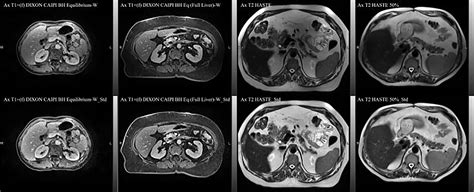

When your physician suspects an issue within your internal organs, they may recommend an MRI of abdomen to gain a clear, detailed picture of what is happening inside. Magnetic Resonance Imaging (MRI) is a sophisticated, non-invasive diagnostic tool that utilizes powerful magnets and radio waves to generate cross-sectional images of the structures in your abdominal area. Unlike X-rays or CT scans, an MRI does not use ionizing radiation, making it a preferred choice for many patients requiring detailed soft-tissue assessment of organs like the liver, gallbladder, pancreas, spleen, and kidneys.

• Contrast Dye: Some scans require a contrast agent (gadolinium) injected intravenously to highlight specific tissues. Notify your technician if you have known allergies or kidney problems.

The most crucial aspect of the process is staying still. Even slight movements can result in blurred images, which may necessitate a repeat of the sequence. For abdominal imaging, the technologist may ask you to hold your breath for short bursts—usually 15 to 20 seconds at a time—to prevent the movement of your diaphragm from distorting the images of the liver and pancreas.

Once the MRI of abdomen is completed, the images are sent to a radiologist, a doctor specially trained to interpret diagnostic scans. The radiologist will analyze the images for signs of disease, inflammation, or structural irregularities. Because an MRI produces a vast number of images, it can take several days for a comprehensive report to be generated and forwarded to your primary care physician or specialist.